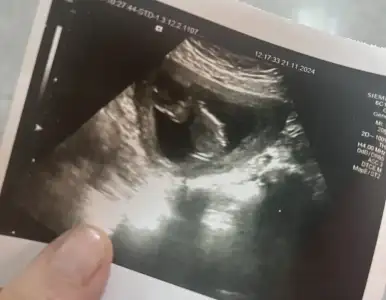

Kızlar herkese iyi günler :) Az önce doktordan çıktım ikili test için gelmiştim cinsiyette sordum ama daha oluşmamıştır dedi bakmadı :) ensede 1.1 dedi bebekte iki büklüm duruyor en iyi açı bu dedi fotosunu verdi bu arada ayakları kıpır kıpırdı. Cinsiyet tahminlerinizi bekliyorum